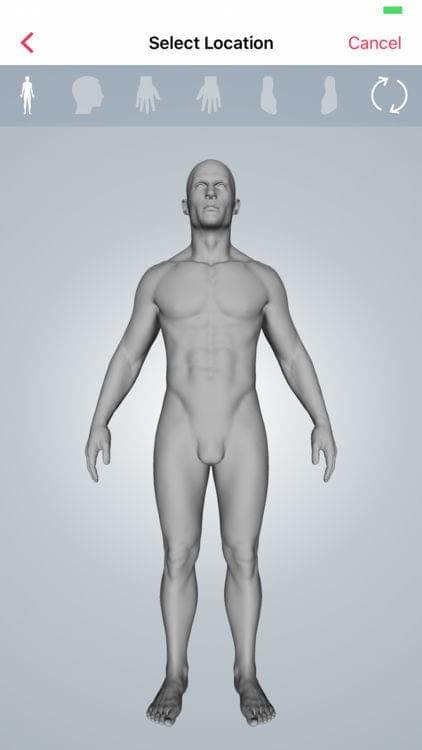

Skin — Body Map

Skin is a digital health imaging app for tracking of moles and skin lesions. The platform is targeted towards academic researchers, physicians and patients looking to integrate a robust sharing platform for the management and surveillance of dermatological conditions. This app gives medical institutions and physicians a secure option to create scalable studies with hundreds of patient participants. The tool is intended to help support the creation of an intelligent model for the accurate diagnosis of skin diseases.